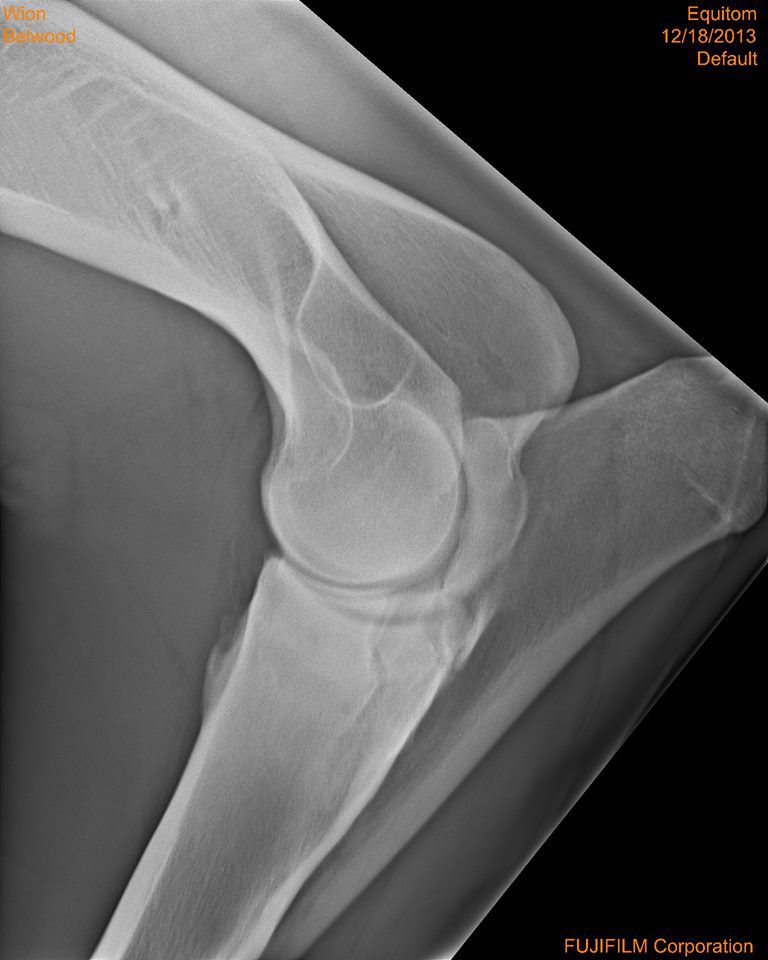

Par conny : le 31/12/13 à 14:11:27

| Dire merci | bon me revoilà avec les radios dites-moi ce que vous en pensez... |

| Dire merci | Je n'y connais pas grand chose, mais il n'y a pas une fracture là où se loge "la boule" de l'articulation ( vers le milieux ) ? Je trouve que c'est bizare à cet endroit... Message édité le 31/12/13 à 14:48 |

| Dire merci | Quercy: je vois ce que tu veux dire mais je suis comme toi, j'y connais rien... nats: comme déjà ecrit, le 1er veto a dit que le cheval n'avait "rien" et le 2eme qu'il fallait l'euthanasier... ici je sais que Al est veto et je pense qu'il doit y en avoir d'autres...donc je prefere voir avec les personnes de confiance, car mon amie ne veut pas euthanasier son cheval et si possible, le donner en tant que tondeuse à gazon... |

| Dire merci | comme déjà ecrit, le 1er veto a dit que le cheval n'avait "rien" et le 2eme qu'il fallait l'euthanasier... Sur les mêmes radio, ces 2 diagnostiques si différents? Et le deuxième véto a forcement commenté les radios avant de proposer l'euthanasie Chez ma jument de 5 ans, le premier véto m'avait aussi dit qu'il n'y avait rien de visible sur les radio malgré le fait qu'elle était positive au test de flexion et lors des radios prises en clinique, il était à (peine) visible qu'il y avait UN bec de perroquet. ça ressemblait un peu à la petite pointe floue à gauche qu'on voit sur ta 2 ème radio, mais bon entre un truc flou anormal et au autre normal... |